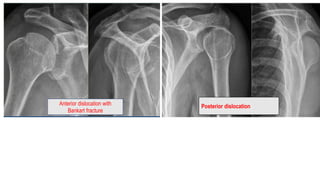

Anterior dislocation with

Bankart fracture

Posterior dislocation

Posterior dislocation-fracture